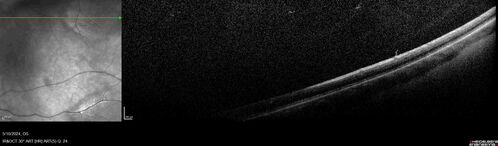

Myelinated Nerve Fiber Layer - Peripheral

43 year old man with floaters